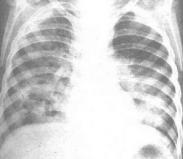

支原體肺炎是肺炎支原體所引起的急性呼吸道感染伴肺炎。肺炎支原體介于病毒和細菌之間,能在無細胞的培養基上生長,無細胞壁,含有RNA和DNA,經代謝產生能量,常與細菌的L型相混淆,兩者的菌落相似。支原體為動物多種疾病的致病體,目前已知人支原體有8種,只有肺炎支原體能引起呼吸道感染,它可發酵葡萄糖等,并能產生溶血素,可在24~48h內完全溶解綿羊和豚鼠的紅細胞,依此可與其他支原體相鑒別。其他支原體可引起泌尿生殖系統感染,一般不侵犯呼吸道。肺炎支原體常引起上呼吸道感染而不伴有肺炎,也可引起無癥狀性感染。國內外的報道均顯示近年來的支原體肺炎發病率有明顯增高趨勢。